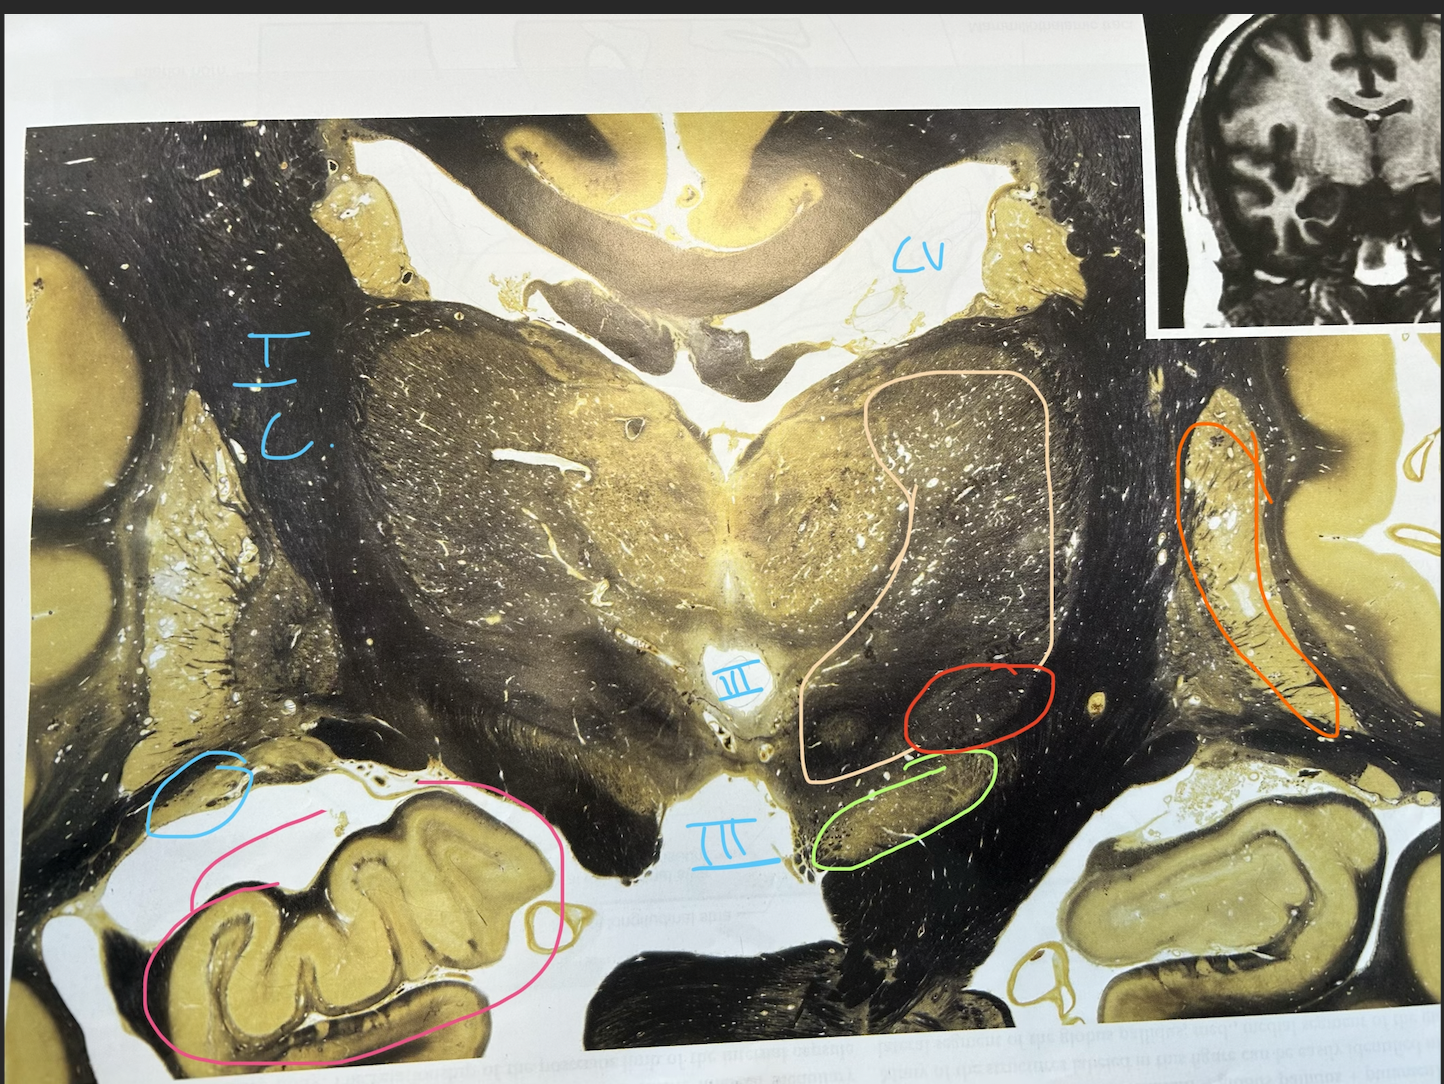

what is purple

fornix

whats in light blue

caudate nucleus

whats in dark blue

optic tract

whats in green

lentiform nucleus (putamen and globus pallidus)

whats in orange ( in green section)

putamen

whats in puple

globus pallidus, internal and external componetns

whats in pink of the left

internal capsule (corticospinal and corticobulbar axons run through here)

caudate nucleus tail

substantia nigra

whats in red ( by the tan)

subthalamic nucleus

whats in orange

whats in pink

hippocampal formation